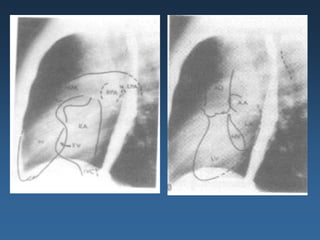

Miocardiopatia hipertrófica

Septo

interventricular

assimétrico.

Hipertrofia

concêntrica

do

ventrículo

esquerdo

RXTX: . ICT normal ou aumentado (HVE)

. Aumento de AE

. Botão aórtico pequeno